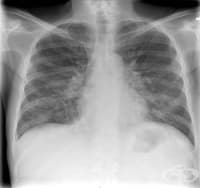

Саркоидозата (болест на Besnier-Boeck-Schaumann) е хронично мултисистемно грануломатозно заболяване,...

Въведение и исторически преглед Саркоидозата (sarco плът, месо; eidos подобно; osis състояние) е мул...